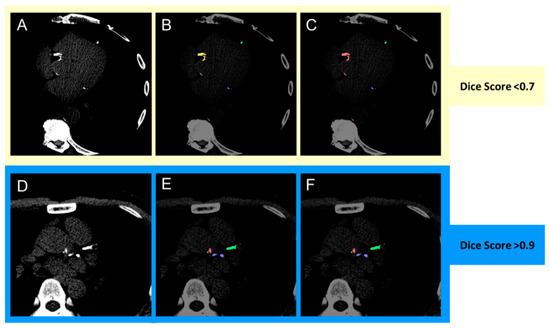

| Structure | Category | Dice Score | ||

|---|---|---|---|---|

| Median | Quartile (1st, 3rd) | p | ||

| Total coronary (LAD + RCA + LCx) | Overall | 0.952 | (0.921, 0.981) | - |

| Male | 0.948 | (0.920, 0.981) | 0.350 | |

| Female | 0.965 | (0.933, 0.980) | ||

| Age < 65 years | 0.950 | (0.913, 0.981) | 0.742 | |

| Age ≥ 65 years | 0.957 | (0.930, 0.977) | ||

| LAD | Overall | 0.971 | (0.930, 1.000) | - |

| Male | 0.963 | (0.919, 1.000) | 0.058 | |

| Female | 0.988 | (0.968, 1.000) | ||

| Age < 65 years | 0.970 | (0.941, 0.999) | 0.980 | |

| Age ≥ 65 years | 0.975 | (0.911, 1.000) | ||

| RCA | Overall | 0.963 | (0.889, 0.991) | - |

| Male | 0.951 | (0.880, 1.000) | 0.633 | |

| Female | 0.977 | (0.923, 0.991) | ||

| Age < 65 years | 0.964 | (0.874, 0.999) | 0.875 | |

| Age ≥ 65 years | 0.959 | (0.899, 0.987) | ||

| LCx | Overall | 0.955 | (0.894, 1.000) | - |

| Male | 0.954 | (0.887, 1.000) | 0.388 | |

| Female | 0.958 | (0.942, 0.998) | ||

| Age < 65 years | 0.954 | (0.905, 0.999) | 0.897 | |

| Age ≥ 65 years | 0.955 | (0.887, 1.000) | ||

| Aortic | Overall | 0.832 | (0.759, 0.897) | |

| Male | 0.802 | (0.760, 0.905) | 0.996 | |

| Female | 0.834 | (0.764, 0.883) | ||

| Age < 65 years | 0.833 | (0.776, 0.933) | 0.204 | |

| Age ≥ 65 years | 0.793 | (0.756, 0.862) | ||